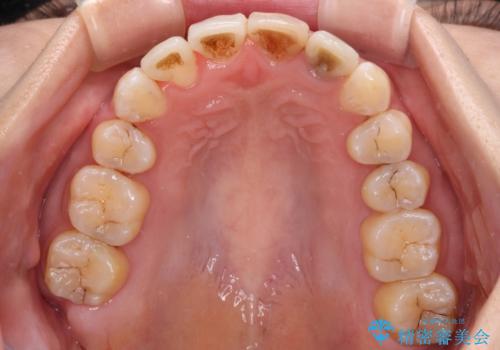

- 重なった前歯を邪魔に感じ、汚れも溜まりやすいことを気にして来院された患者様です。

右上前から2番目の歯が内側に転位しているため、上顎の正中は右にずれていました。

右上4番目の歯を抜歯し、上顎裏側に補助装置を装着して左の歯列全体を後方に移動させながら、正中を合わせるようにして行くこととしました。

内側に転位していた歯はきれいに歯列に収まり、清掃性が著しく改善しました。

元々神経の失活してしまっている前歯2本は変色が目立つようになってきたため、今後セラミッククラウンによる補綴治療を行う予定です。